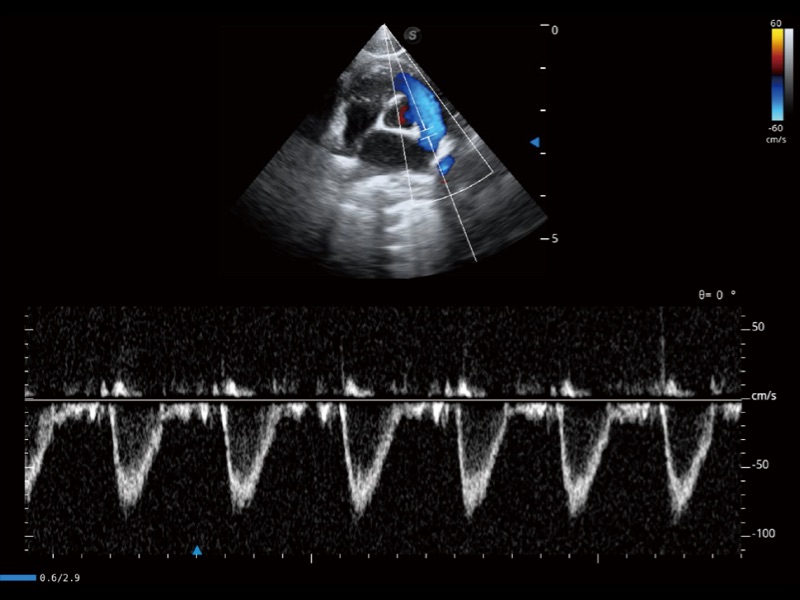

能够基于左心室壁追踪和辛普森法,自动计算射血分数,支持多个可移动点描迹,与手动测量相比,极大节省了动物医生的时间和精力。

具备多种协议可选,同时支持17阶段划分法和专业的SE报告。